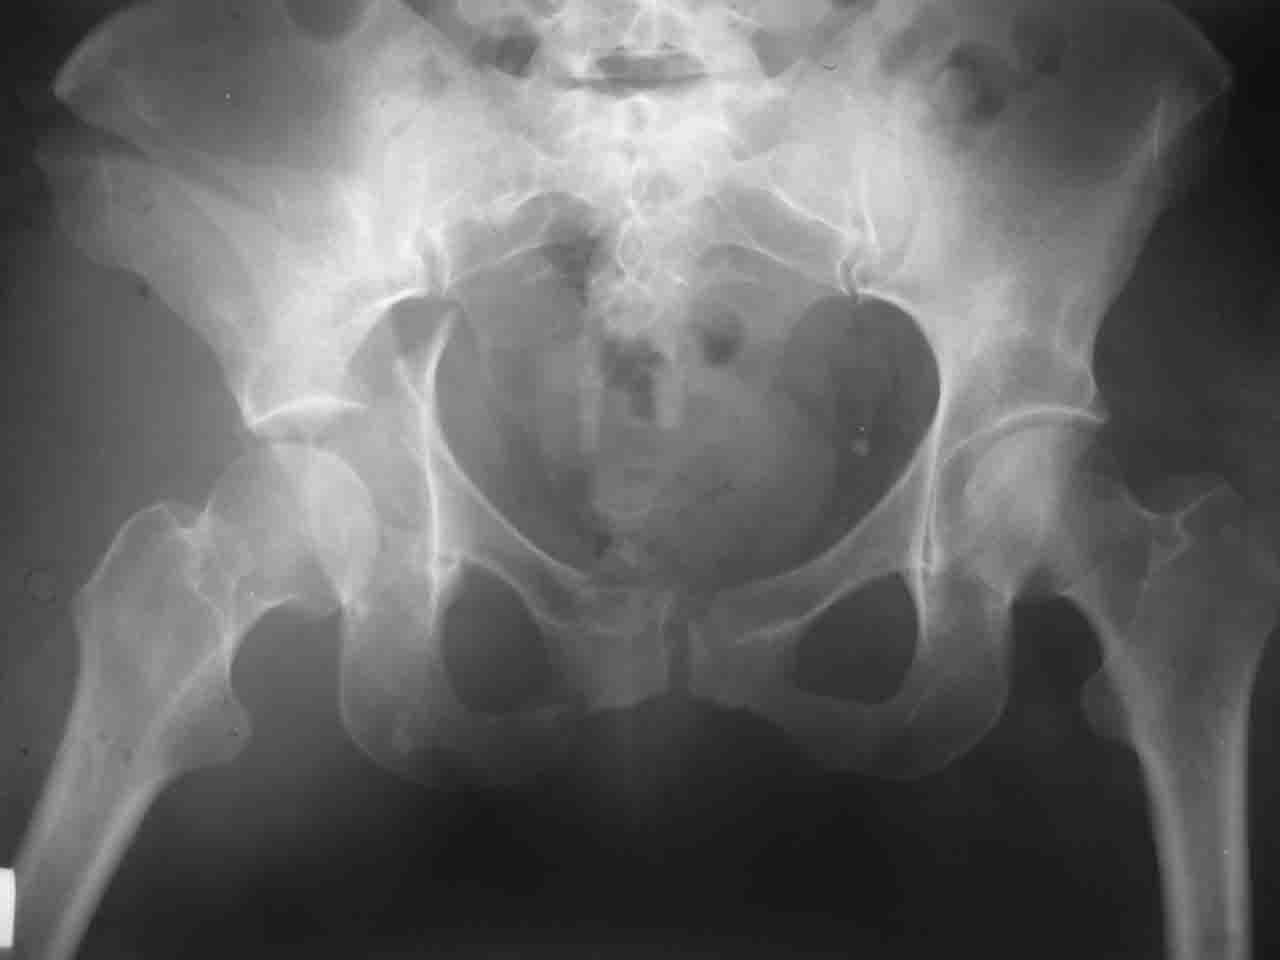

Re: Перелом вертлужной впадины

Снимки и схема